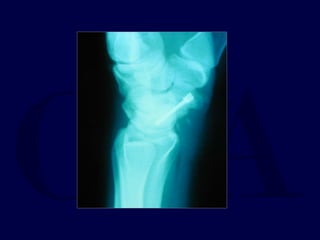

ORIF: volar approach

Herbert screw with

Final screw placement